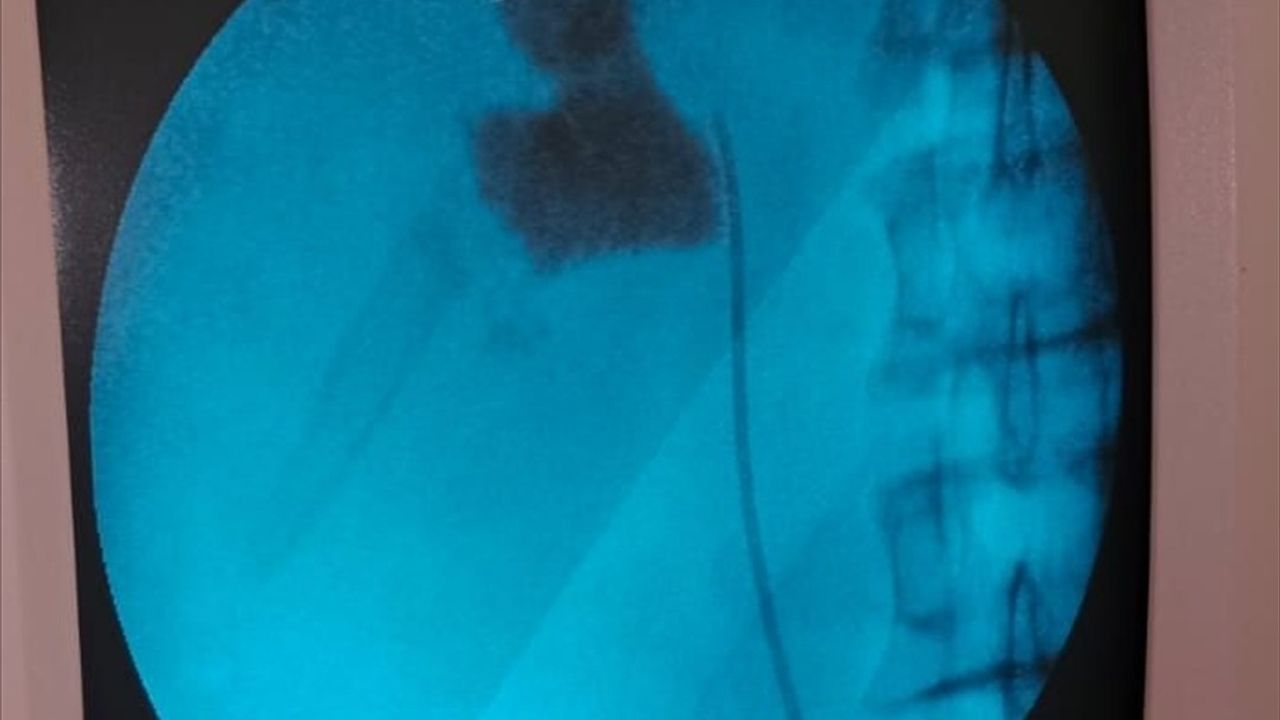

Kırşehir'de, Eğitim ve Araştırma Hastanesi'nde bir hastanın böbreğindeki 6 santimetrelik taş, kapalı ameliyat yöntemiyle alındı.

Hastaneye başvuran İlhami Çakır'ın yapılan kontrollerinde, sol böbreğinde 6 cm boyutunda bir taş tespit edildi. Üroloji Kliniği'nden Uzm. Dr. Talip Göktaş ve ekibi, kapalı böbrek taşı yöntemi PNL ile başarılı bir ameliyat gerçekleştirdi.

Ameliyat sonrası bir gün içinde taburcu olan Çakır, operasyon ekibine teşekkür etti. Uzm. Dr. Göktaş, hastaların bu yöntemle açık ameliyatlara göre daha hızlı bir iyileşme süreci yaşadığını belirterek, "Hastamız 1 gün sonra taburcu edildi. Bu yöntemle hastalarımız daha konforlu bir şekilde süreç atlatabiliyor. Son 5 yıl içinde hastanemizde 50'nin üzerinde bu tarz başarılı ameliyat gerçekleştirdik," ifadesini kullandı.